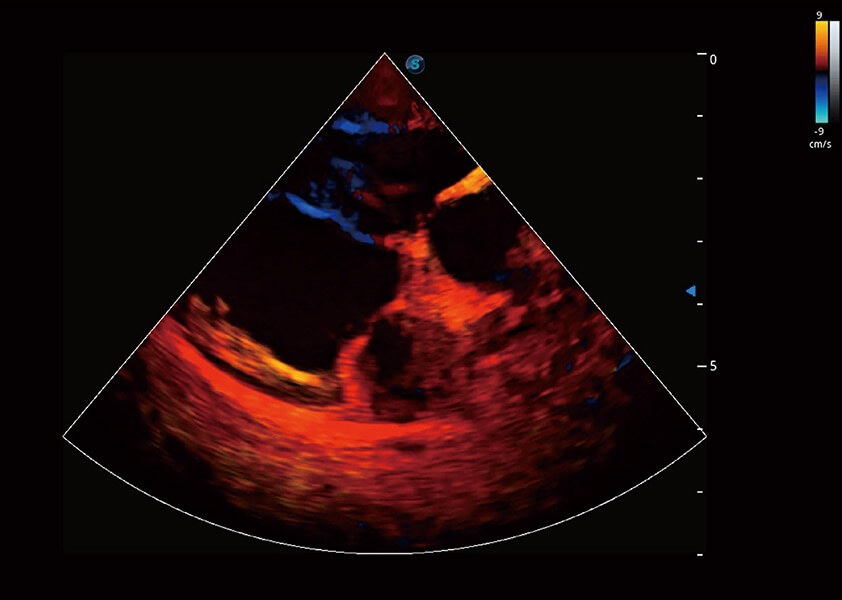

优异的基础图像

(犬)四腔心血流

(犬)心脏组织多普勒